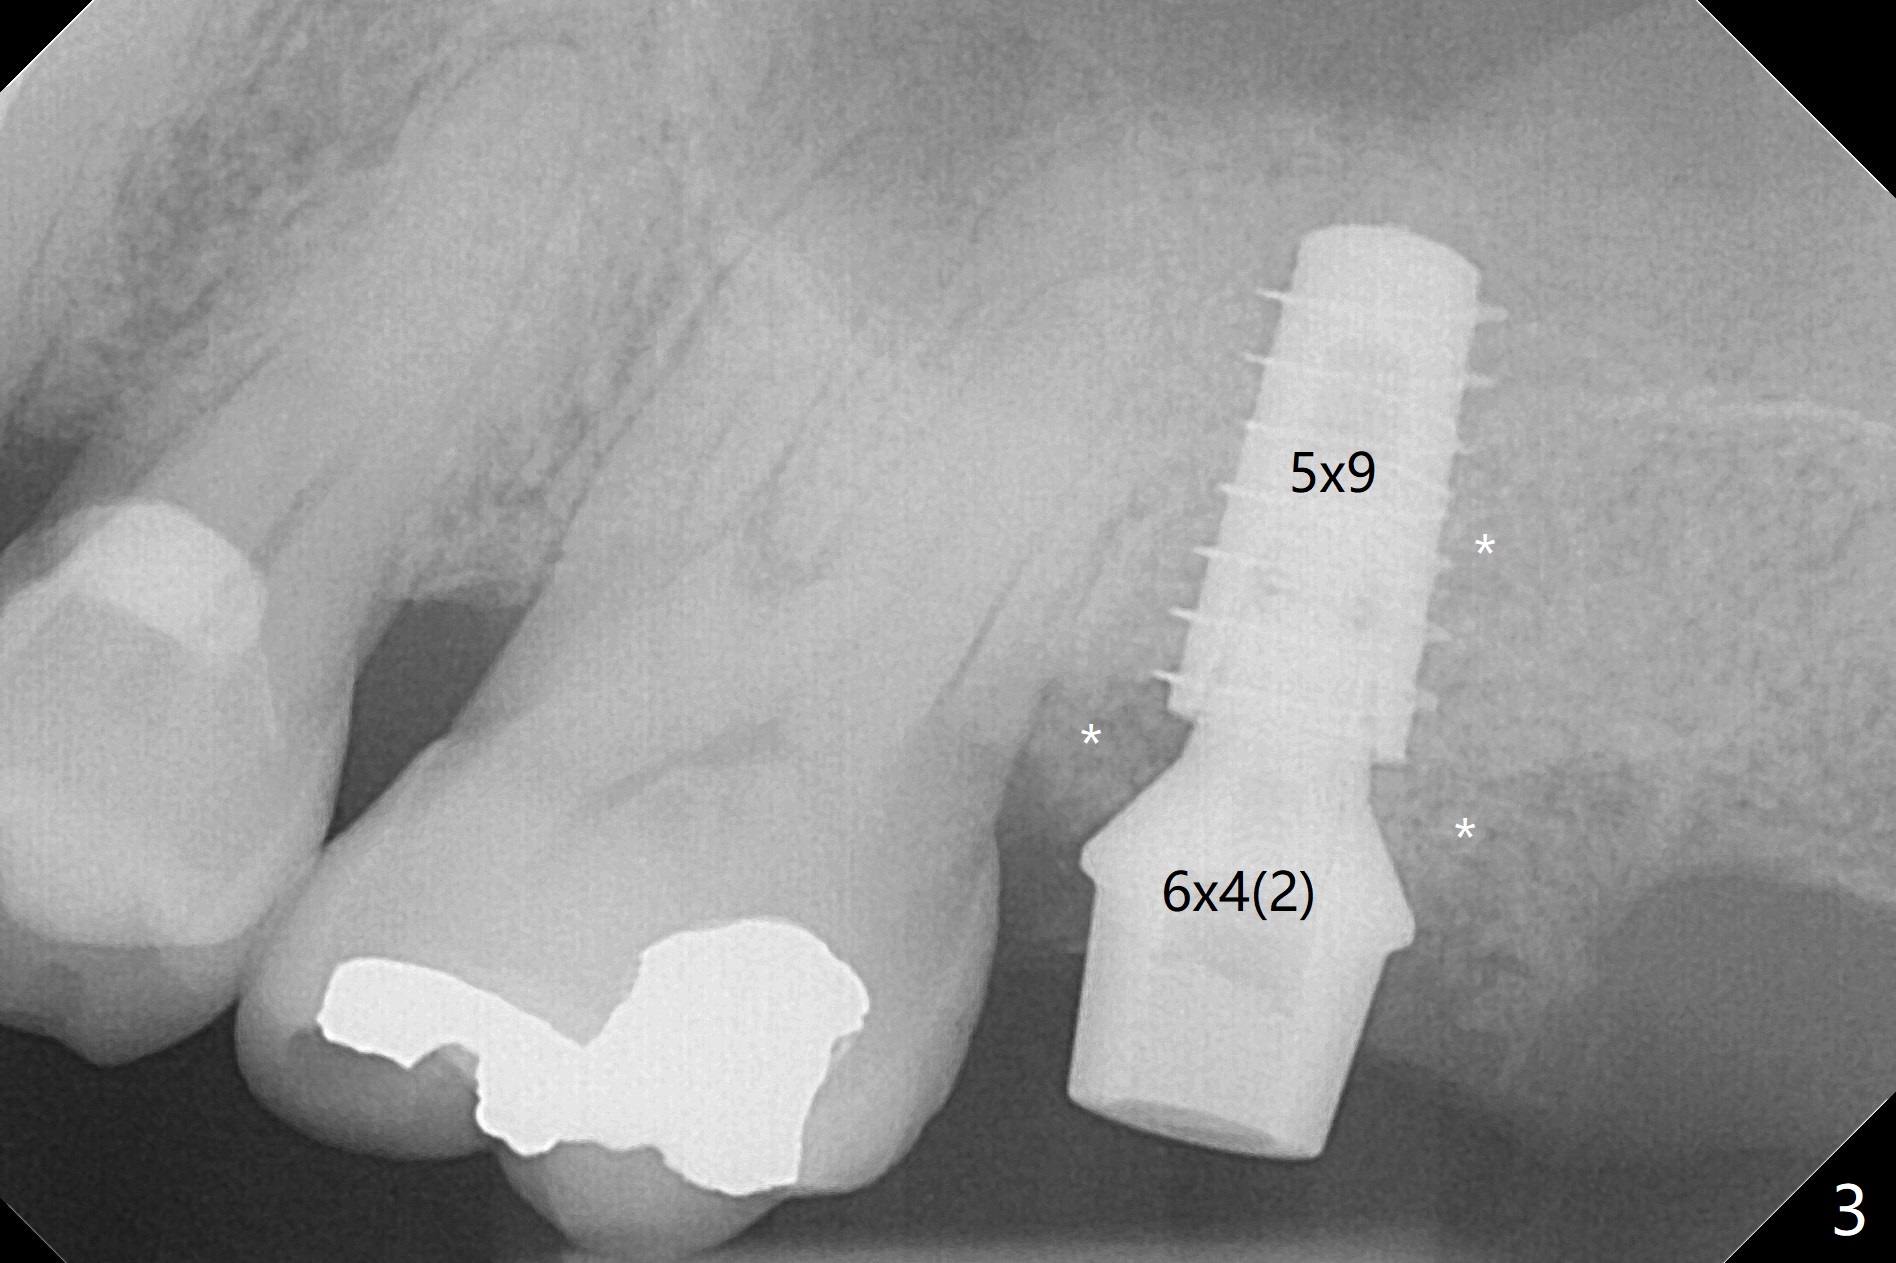

Designed osteotomy depth is 7.3 mm IS drill with 4 rings at #15. In fact osteotomy is created using 2.2 mm drill with 2 rings (sinus membrane barely visible from the osteotomy) and 3-4 mm ones with 3 rings. With an amalgam carrier of bone graft, sinus lift is initiated with 4x9 mm dummy implant (Fig.1). After loaded with totally 5 amalgam carriers of bone graft repeatedly with the 4x9 mm dummy implant, a 5x9 mm implant is placed with ~ 25 Ncm. After insertion of a 6x4(2) mm abutment, sticky bone cut into pieces (Fig.2) is inserted to peri implant space (Fig.3 *), followed by PRF and an immediate provisional. The latter dislodges 7 days postop; the socket starts to heal (Fig.4); the bone graft seems to be fixed in place. The provisional is reseated (no cement, Fig.5) without fear of its dislodgement again. The patient returns for cleaning 1 year 7 months postop (Fig.6,7). The socket heals, while the abutment is incompletely seated (Fig.7 <). Percussion at #18 disappears post RCT, whereas periapical radiolucency appears post RCT (compare Fig.8,9). When the 6x4(2) mm incompletely seated abutment is removed, the implant well is dirty. The smaller abutment with longer cuff is seated fully (Fig.10).